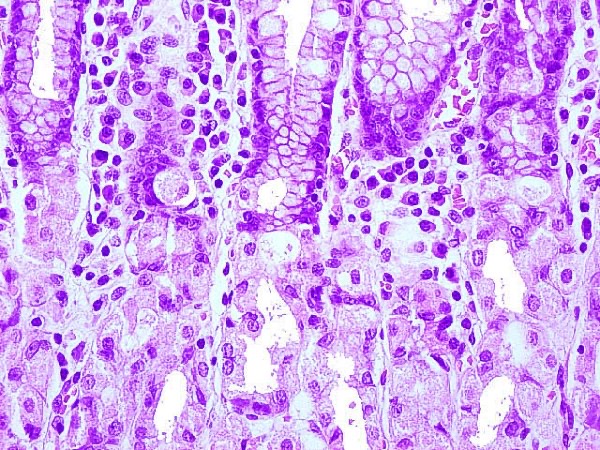

Las células diferenciadas en el revestimiento gástrico incluyen las células principales (oxínticas), las células parietales, las células endocrinas y las células mucosas. Cada tipo celular tiene un papel específico en la secreción de enzimas digestivas, la producción de ácido clorhídrico, la regulación hormonal y la producción de moco protector.

Las células progenitoras gástricas se dividen y dan lugar a células más especializadas a medida que se desplazan hacia la superficie del revestimiento gástrico. Durante este proceso, las células se someten a cambios genéticos y bioquímicos que las hacen adquirir características específicas y funciones especializadas.